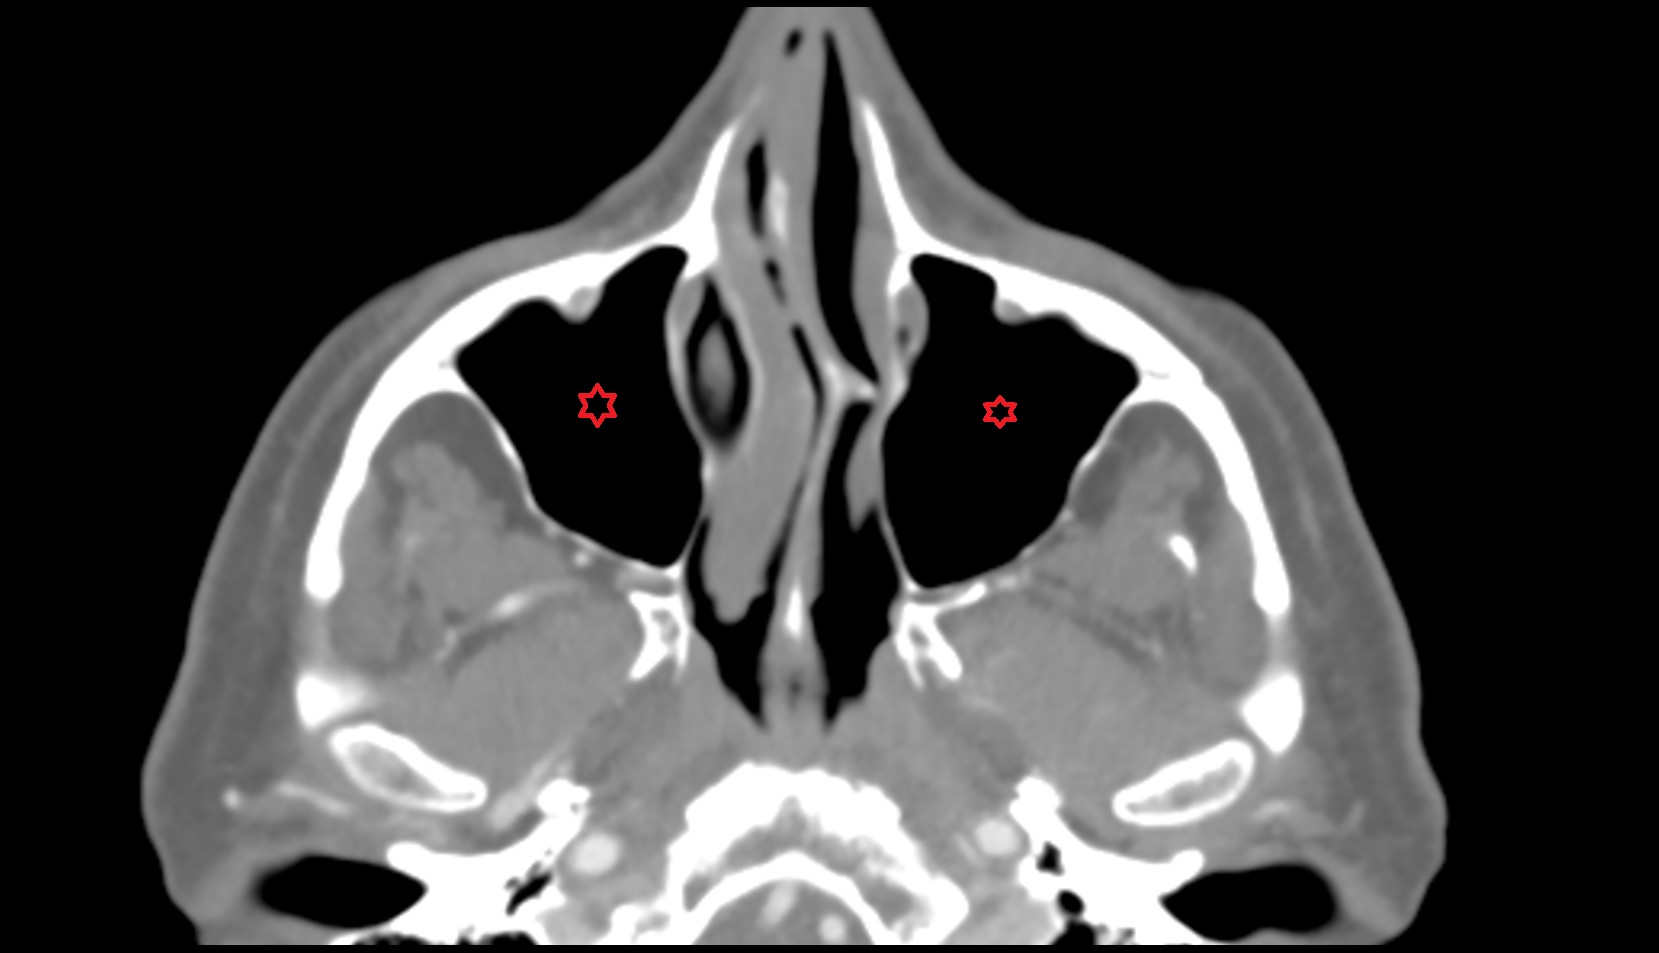

- Maxillary sinus

- Middle nasal concha

- Inferior nasal concha

- Nasal septum